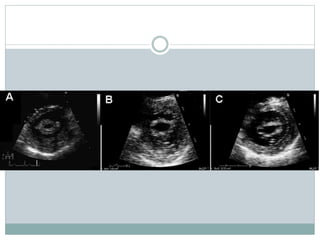

 Commissural fusion

PSAX echo scanning of valve

Important in distinguishing

degenerative from rheumatic

valve

Complete fusion indicate

severe MS

Narrow diastolic opening of

valve leaflets